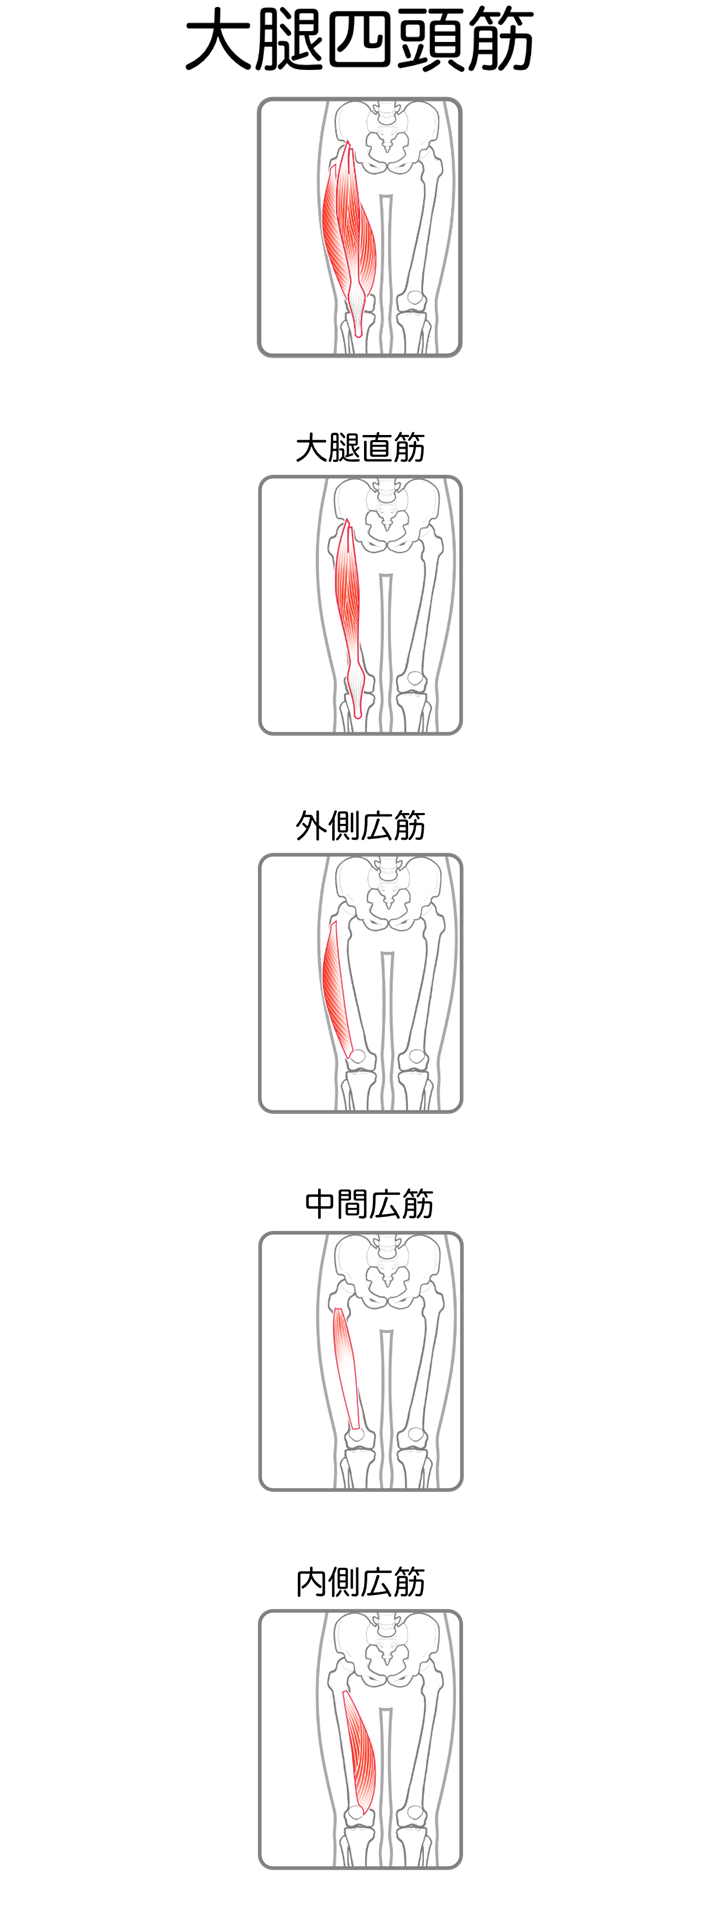

大腿四頭筋

| 起始 | 大腿直筋-下前腸骨棘, 寛骨臼上縁 外側広筋-大腿骨 大転子, 大腿骨 外側面 中間広筋-大腿骨前面, 外側面 内側広筋-大腿骨 内側面 |

| 停止 | 膝蓋骨底, および両側縁, 脛骨粗面 |

| 神経 | 大腿神経L2-4 |

| 作用 | 膝関節伸展 |

臨床でよく経験するのは、大腿直筋の短縮です。

大腿直筋は股関節と膝関節にまたがる2関節筋であるため、股関節屈曲だけでなく骨盤前傾にも影響します。

同じ骨盤前傾姿勢であっても、その原因が腸腰筋由来なのか、大腿直筋由来なのかで介入ポイントは大きく変わるため、両者の鑑別は非常に重要です。

また、膝関節伸展不全(エクステンションラグ)と内側広筋(VMO)の筋活動には強い関連があり、膝関節術後のリハビリテーションでは内側広筋の促通を積極的に行っています。

実際に担当した方でも、膝関節伸展不全があり、歩行時に膝折れが出現していたケースがありました。

膝関節伸展可動域の確保と、パテラセッティングによる内側広筋の促通を行うことでエクステンションラグが改善し、歩行時の膝折れも軽減しました。